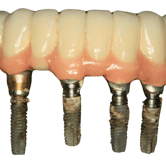

Edentulismo completo

El edentulismo completo es la ausencia total de dientes en una o ambas arcadas.

Los pacientes tienen dificultad para masticar, hablar y pueden sentirse incómodos con su apariencia.

El tratamiento puede incluir la colocación de una prótesis completa sobre implantes, proporcionando una solución fija y estable